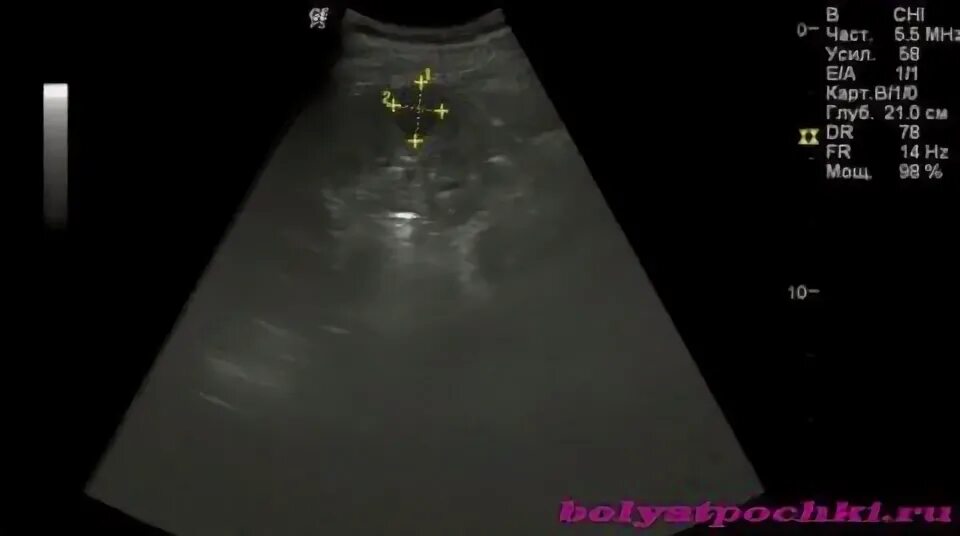

Гиперэхогенное образование в почке что это